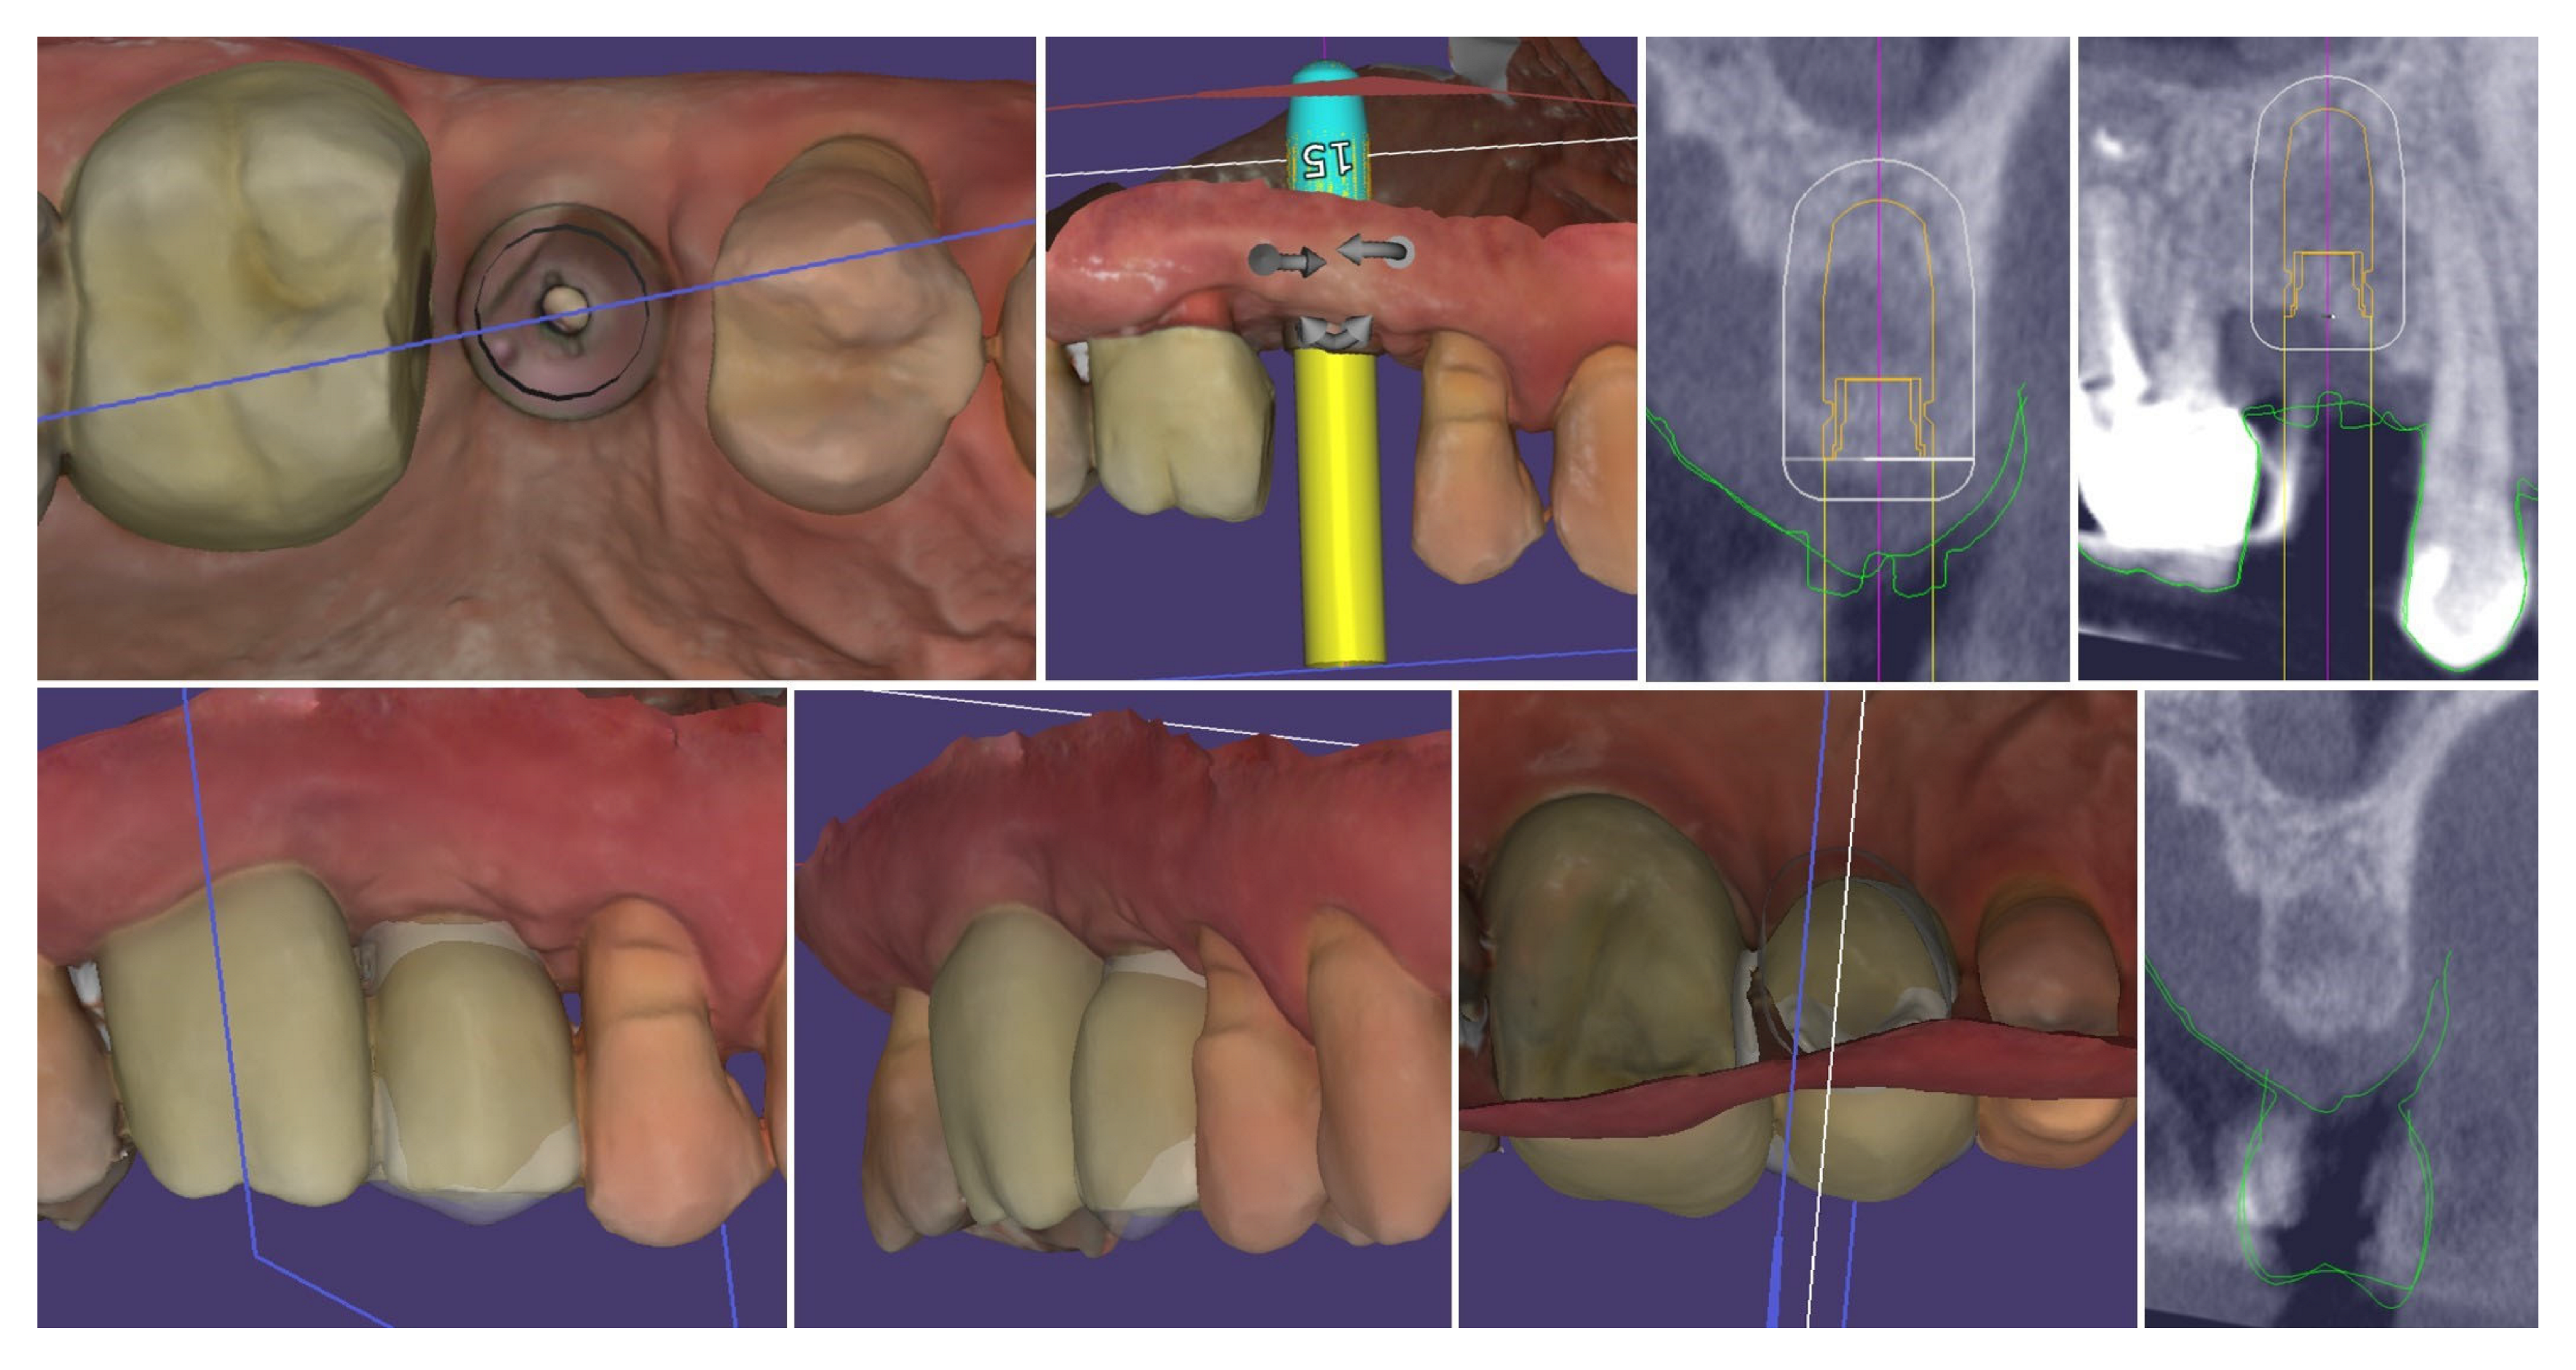

| Timepoint | Horizontal Thickness (mm) | Vertical Thickness (mm) | Clinical/Radiographic Findings | |

|---|---|---|---|---|

| 1 | Baseline (Day 0) | 2.3 | 2.4 | Initial thin buccal tissue |

| 2 | 2 weeks post-op | Uneventful healing, stable mucosal margin | ||

| 3 | 3 months post-op (with provisional) | 3.4 | 3.4 | Increased thickness, stable bone and mucosa |

| 4 | 4 months post-provisional | 3.5 | 3.6 | Stable peri-implant mucosa around provisional crown |

| 5 | 8 months post-op (final crown) | 3.5 | 4.1 | Final crown placed, harmonious soft tissue contours, and stable crestal bone |

| 6 | 14 months post-definitive | Long-term stability of soft tissue and crestal bone confirmed |